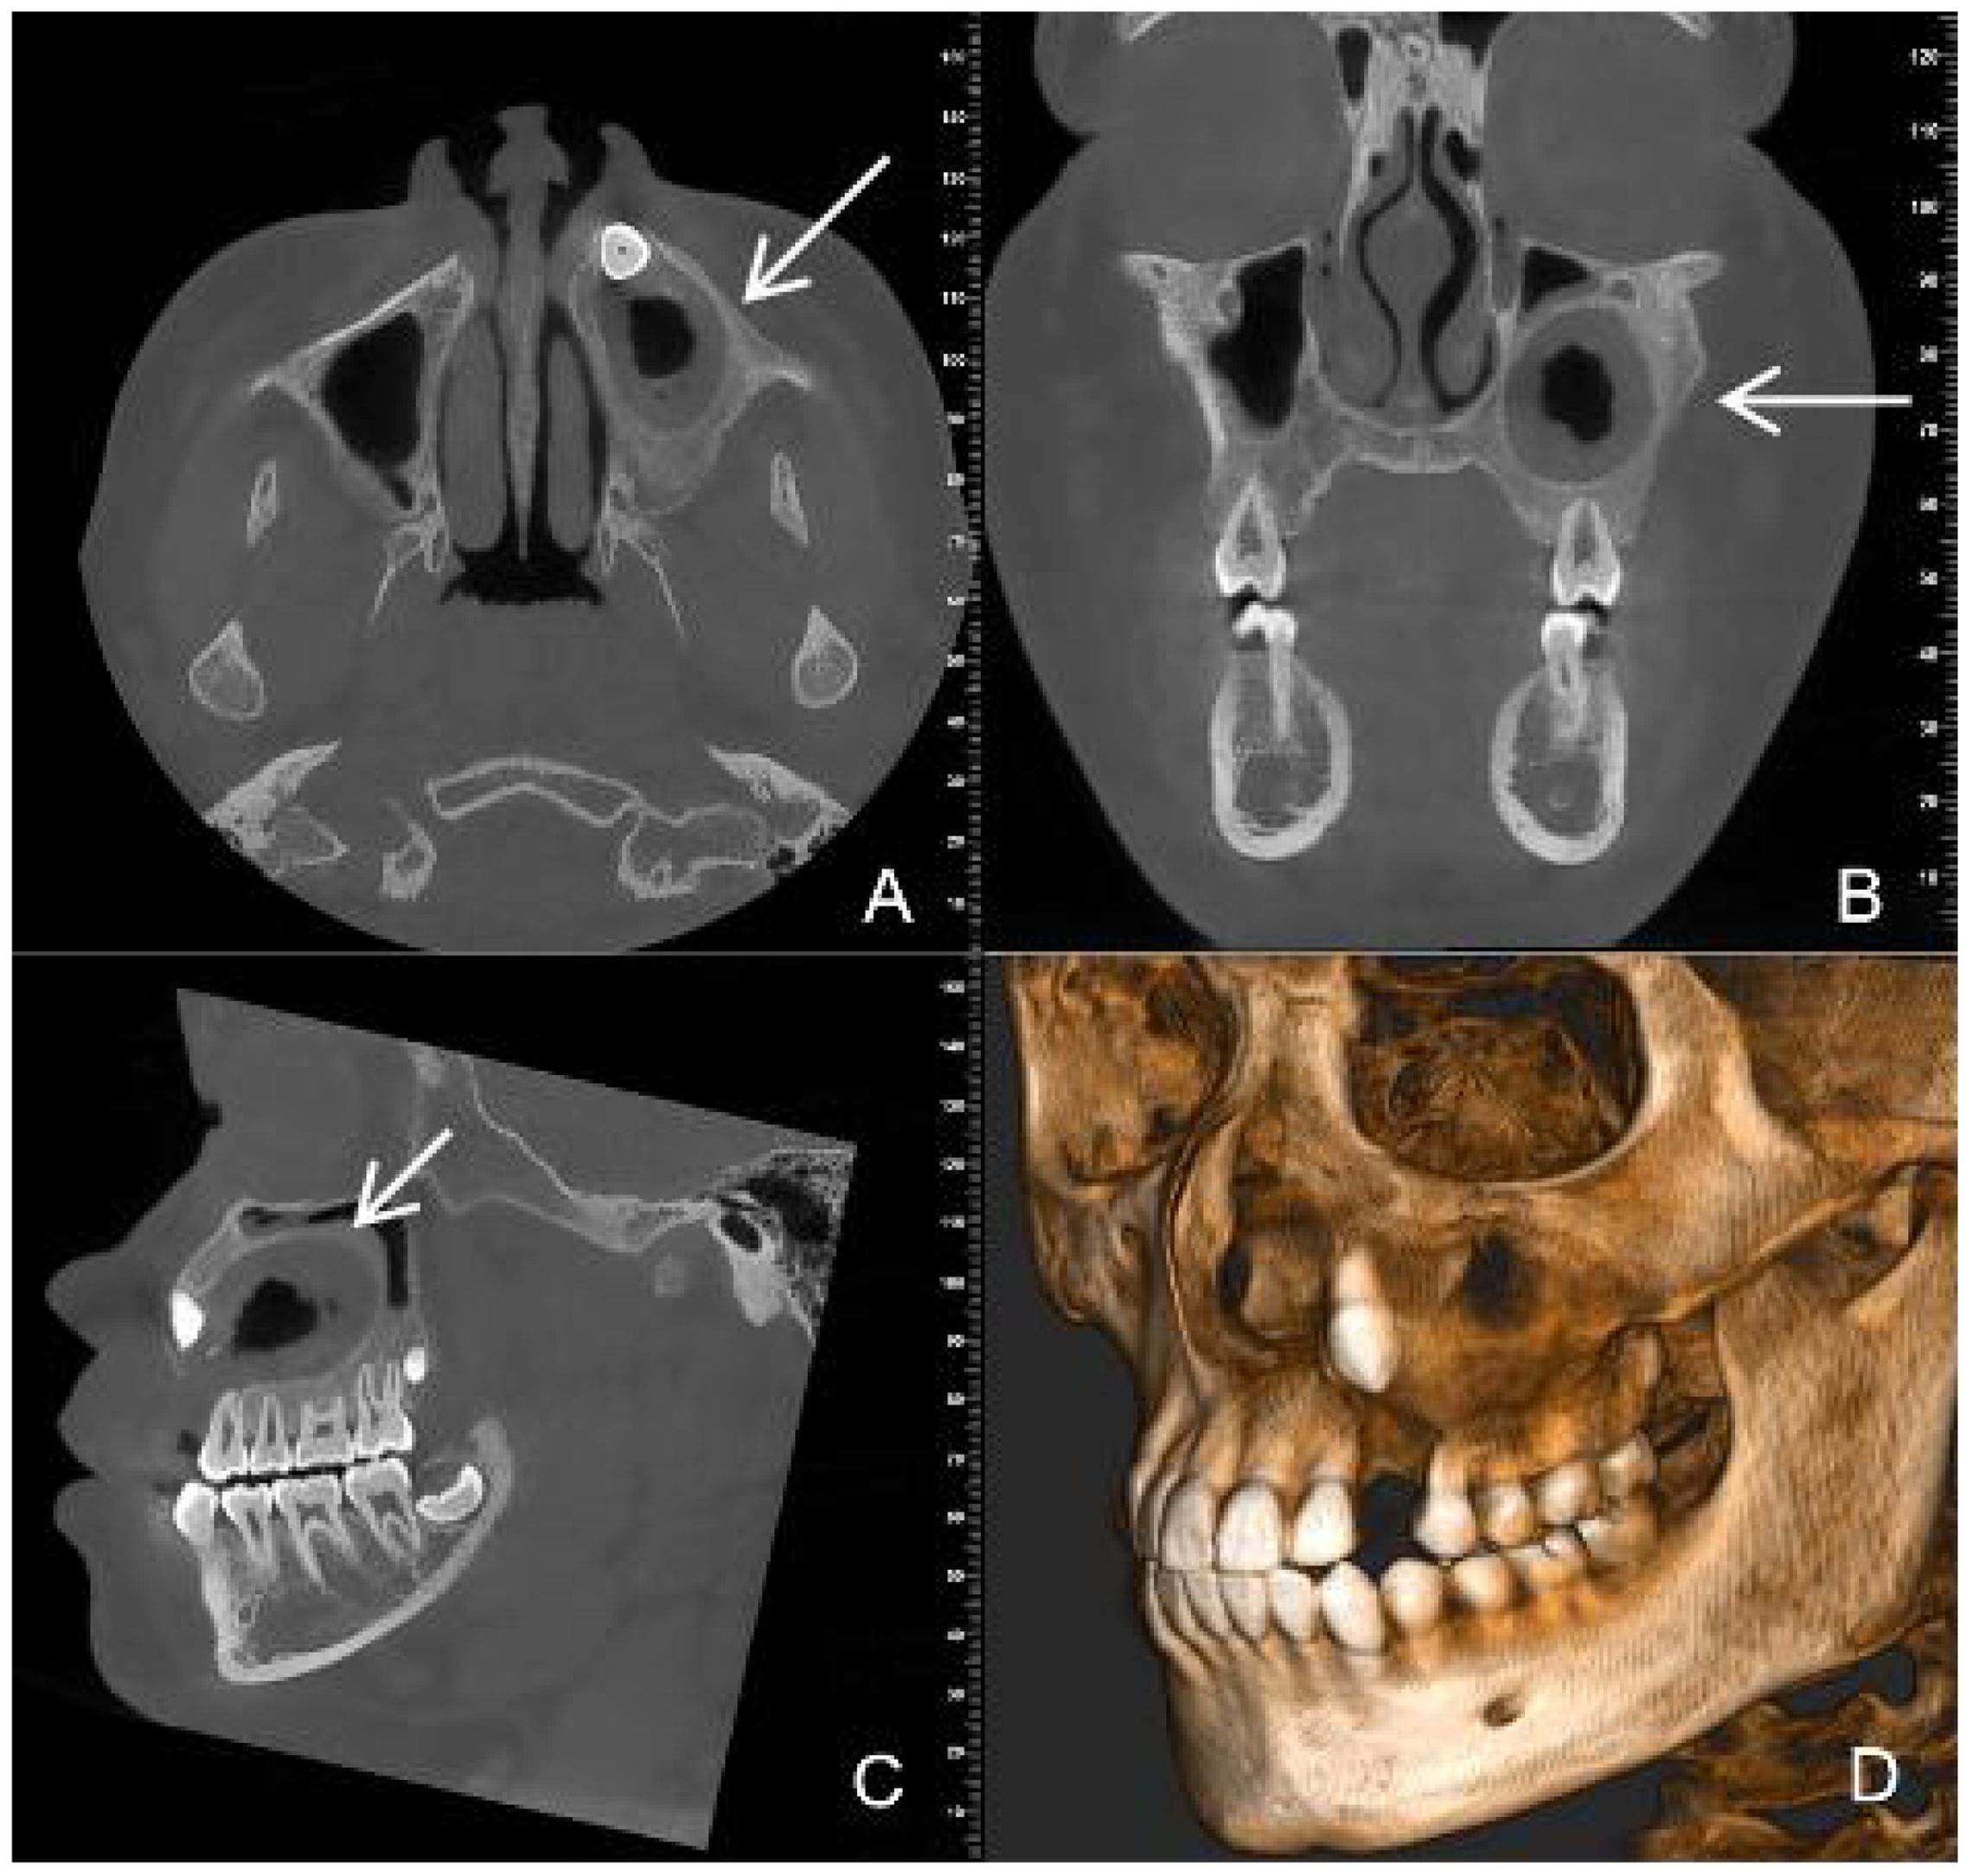

Dentinogenic ghost cell tumor (DGCT) is a rare odontogenic neoplasm that presents with nonspecific clinical manifestations and imaging features. It is more prevalent in elderly patients, with cases in children being extremely rare. This article presents a case study of a 10-year-old male patient who exhibited symptoms of swelling and pain in the left cheek for a duration of two weeks. Cone beam computed tomography (CBCT) demonstrated a hypodense lesion involving the left maxilla, with extension into the maxillary sinus and buccal cortical expansion. The patient underwent decompression, and histopathological examination of the intraoperative specimen suggested a diagnosis of calcifying odontogenic cyst (COC). One year after decompression, the patient underwent a tumor resection and the diagnosis of DGCT was confirmed by the post-operative pathology. Six months after tumor resection, CBCT showed complete bone remodelling in the lesion area. The patient is currently undergoing regular follow-up. This case provides an important reference for the diagnosis and treatment of pediatric DGCT, helping clinicians to develop individualised treatment plans.